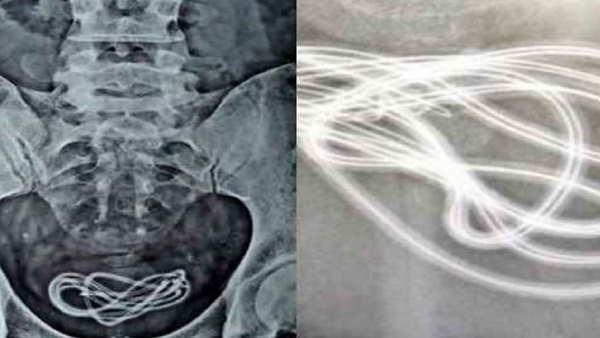

मार्च के महीने में एक रात शराब के नशे में धुत होकर उसने मोबाइल चार्जर का तार काट लिया और अपने गुप्तांग के अंदर घुसाने लगा। तार तकरीबन एक फुट लंबा तार शरीर के अंदर चला गया। केबल यूरिनरी ब्लैडर में जाकर अटक गई। लोक-लाज के भय से उसने इस घटना के बारे में किसी को भी नहीं बताया। लेकिन बीते 15 दिन से उसे पेशाब रुकने और पेट दर्द की परेशानी शुरू हो गई। इसके बाद आनंद एक निजी नर्सिंग होम पहुंचा और डॉक्टर को अपनी इस हरकत के बारे में बताया।

जांच के बाद डॉक्टर ने ऑपरेशन कराने की सलाह दी। बीते शुक्रवार को यानी कि पांच जून को डॉक्टर ने ऑपरेशन के बाद उसके यूरिनरी ब्लैडर में फंसे तार को बाहर निकाला। इलाज के बाद मरीज की हालत खतरे से बाहर है। ऑपरेशन करने वाले चिकित्सक डॉ. सुनील कुमार का कहना है कि अगर कुछ दिन और तार अंदर रहता तो पेशेंट की जान भी जा सकती थी। उनका मानना है कि इस तरह की हरकत मानसिक विकृति के शिकार लोग ही कर सकते हैं।